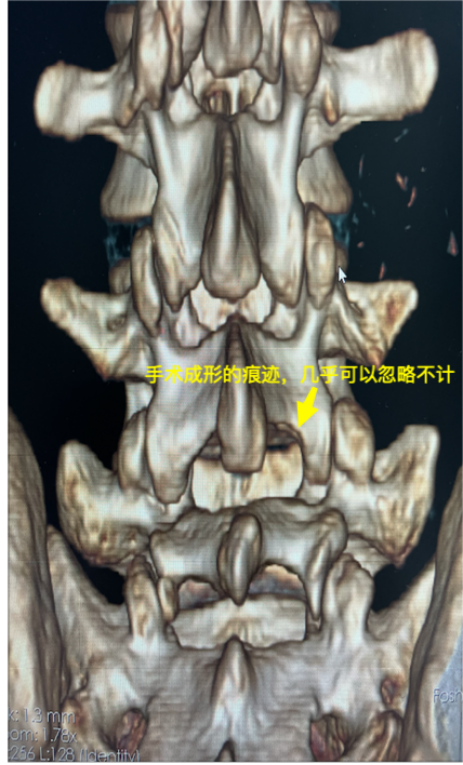

手术微创性保证,并未损伤关节突关节

术前术后CT对比可见突出椎间盘已被成功摘除